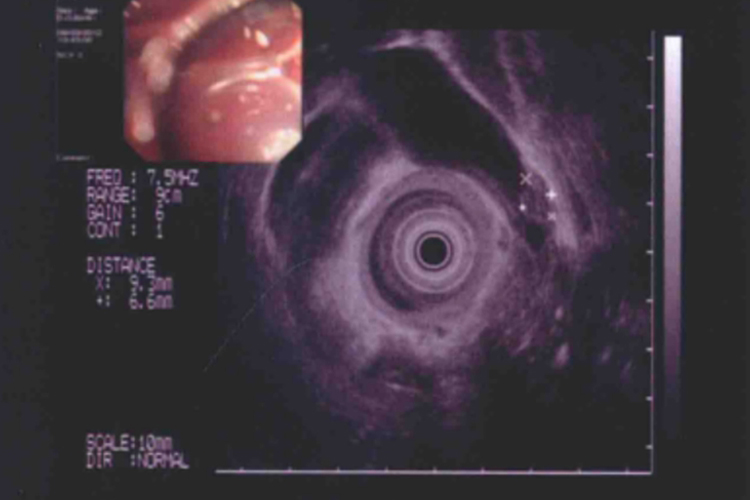

胆囊腺肌症B超或超声内镜检查对明确该病有重要的价值,其声像图特点为胆囊壁增厚,呈弥漫性、节段性改变或局限性改变;增厚的胆囊壁内,可见无回声暗区或回声增强区(胆固醇沉积);合并壁间结石和胆囊结石,可出现相应的改变。